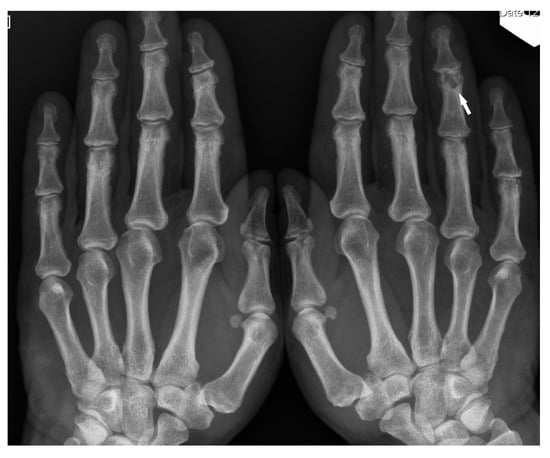

Only the radiological pattern of the lesions in the phalanges of the hands and feet, resembling a lace on X-ray, is described as characteristic of bone sarcoidosis.

The radiographic appearance of phalanges occupied by sarcoidosis includes lytic lesions of various sizes, called cysts. Cystic lesions, mostly punched-out, may be accompanied by soft tissue nodules. The presence of large cysts increase the risk of pathological bone fracture [20] (Figure 6a,b). Numerous small cysts are more frequently observed. The articular surfaces are preserved, although cysts located in the subchondral layer might mimic erosions (Figure 7). Periosteitis is uncommon.

Figure 7. X-ray of the hands, PA. Unilateral osteolytic-cystic lesions in the subchondral layer of the middle phalanx of the 4th finger of the left hand (white arrow).